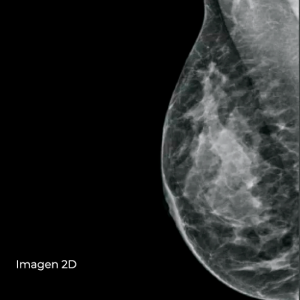

Cree estudios de diagnóstico integrales con un nivel de detalle clínico y una sensibilidad excepcionales mediante la técnica de obtención de imagen en 2D con contraste (CE2D). Esta herramienta avanzada combina los estudios de CE2D y 3D Mammography™ para mejorar la capacidad de identificar cánceres precozmente.

Se ha demostrado que la mamografía con contraste permite detectar cánceres que no se ven claramente en una mamografía convencional. La combinación de la obtención de imagen en 2D con contraste (CE2D) y una exploración por tomosíntesis permite la localización y la evaluación morfológica de las lesiones, lo que potencia el valor del procedimiento de CE2D en la identificación de posibles tumores malignos.

Modo CE2D: Obtención de imagen en 2D con contraste